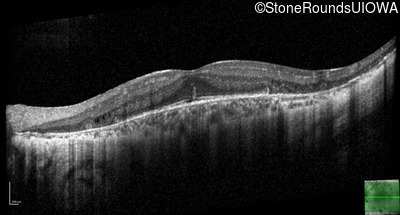

Optical Coherence Tomography - Left - 20/25 +1

Exemplar / OCT Stack